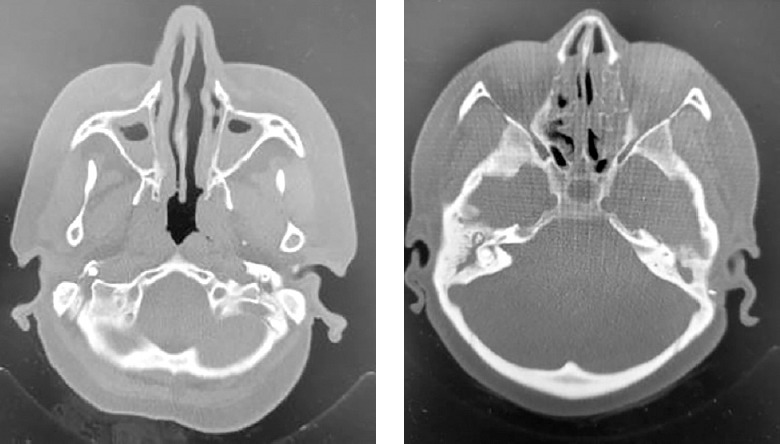

A 47-year-old female patient presented at our adult allergy and immunology outpatient clinic with complaints of cough, sputum production, and shortness of breath. Her medical history included asthma and allergic rhinitis for 15 years. The patient was using salmeterol fluticasone 500/50 µg 2 × 1, desloratadine 5 mg 1 × 1, montelukast 10 mg 1 × 1, and salbutamol inhaler 100 µg 4 × 1 for the diagnosis of asthma and allergic rhinitis. The patient has had two asthma exacerbations requiring oral corticosteroids (OCS) (at least 3 days or longer) in the last year. There was also a history of frequent antibiotic use due to frequently recurring pulmonary infections. Rhonchi were detected on both lungs during the physical examination. At the time of presentation at the clinic, the patient’s asthma was not under control, with an asthma control test (ACT) score of 5. In laboratory tests, total IgE, blood eosinophil count and house dust mite specific IgE level was high, and IgG2 and IgG4 levels were low. In flow cytometric analysis, CD3, CD4, CD8, CD16/56, CD19 values were within normal range. Both PR3 anti-neutrophil cytoplasmic antibody (ANCA) and MPO ANCA were detected negative. HIV serology was detected negative. Complete urinalysis examination and other laboratory tests were within normal range. Bronchiectasis in both lungs was determined on thoracic computed tomography (Figure 1). On paranasal sinus computed tomography, findings were consistent with widespread sinusitis in all paranasal sinuses (Figure 2). In the pulmonary function test, forced expiratory volume in 1 s (FEV1) was 34%, forced vital capacity (FVC) was 53%, and the FEV1/FVC ratio was 55%. The patient was diagnosed with uncontrolled hypereosinophilic severe persistent asthma and immune deficiency (immunoglobulin G subclass deficiency). The patient had frequent lung infections under antibiotic prophylaxis with trimethoprim-sulfamethoxazole 80/400 mg 3 days per week. Treatment was started of benralizumab 30 mg/subcutaneously once a month for the diagnosis of uncontrolled hypereosinophilic severe persistent asthma, and IVIG 30 g every 21 days for the diagnosis of immunodeficiency (ACT score at 1 year: 20). After 1 year of benralizumab treatment, improvements were observed in respiratory function tests (FEV1: 46%, FVC: 65% and FEV1/FVC ratio: 64%) and blood eosinophil count (at 12th month: 0 cell/ml). The IVIG treatment resulted in decreased antibiotic use for recurrent lung infections in the 1-year period. The clinical and laboratory findings of the patient are shown in Table 1.